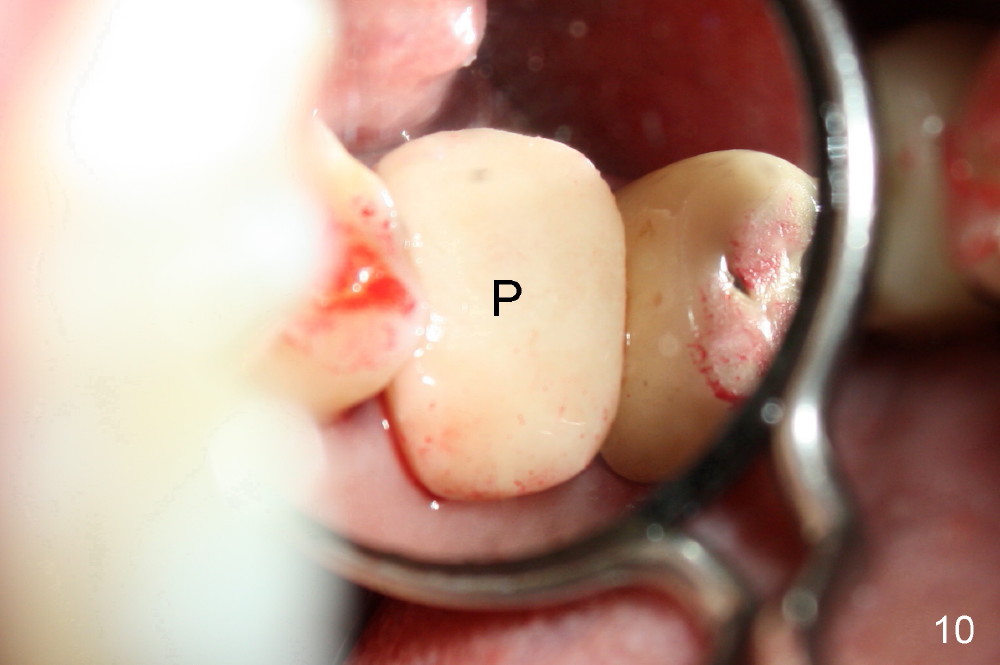

A 66-year-old lady requests restoring a broken tooth (Fig.1). Osteotomy is initiated in a thin septum (Fig.2 (occlusal mirror view) S) by sectioning, drilling and tapping (Fig.3 T). When 7x17 mm tap is removed, the osteotomy is found to form basically in the middle of socket (Fig.4 O). The apical portion of three sockets (Fig.5: MB, P and DB (not labeled) is packed with mixture of autogenous bone and allograft. When a 7x14 mm implant is placed, there are buccal and lingual gaps (Fig.6 *). The latter are bone grafted again (Fig.8 *) and require a coverage. After placement of a 4x3 mm abutment (Fig.7,8 A), an immediate provisional is fabricated (Fig.9 tissue surface view) to cover the remaining sockets (Fig.10 (occlusal mirror view), 11 (buccal view)). The provisional is infra-occlusal, i.e., load-free (Fig.11). The buccal and lingual aspects of the socket are covered by fresh epithelium 8 days postop (Fig.12 <). The implant appears to have osteointegrated 4 months postop (Fig.13). The tooth #16 appears to have shifted mesially. It is difficult to prepare for #15 crown. Luckily the patient agrees to have it extracted because of persistent sensitivity after MO composite. The definitive crown at the site of #15 is cemented 6 months postop (Fig.14).